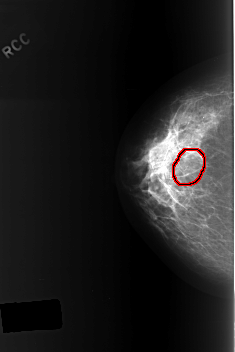

ics_version 1.0 filename C-0365-1 DATE_OF_STUDY 19 8 1996 PATIENT_AGE 52 FILM FILM_TYPE REGULAR DENSITY 2 DATE_DIGITIZED 13 10 1998 DIGITIZER LUMISYS LASER SEQUENCE LEFT_CC LINES 5536 PIXELS_PER_LINE 3744 BITS_PER_PIXEL 12 RESOLUTION 50 NON_OVERLAY LEFT_MLO LINES 5288 PIXELS_PER_LINE 3928 BITS_PER_PIXEL 12 RESOLUTION 50 NON_OVERLAY RIGHT_CC LINES 5624 PIXELS_PER_LINE 3752 BITS_PER_PIXEL 12 RESOLUTION 50 OVERLAY RIGHT_MLO LINES 5584 PIXELS_PER_LINE 3712 BITS_PER_PIXEL 12 RESOLUTION 50 OVERLAY |

FILE: C_0365_1.RIGHT_CC.OVERLAY TOTAL_ABNORMALITIES 1 ABNORMALITY 1 LESION_TYPE CALCIFICATION TYPE AMORPHOUS DISTRIBUTION CLUSTERED ASSESSMENT 4 SUBTLETY 4 PATHOLOGY BENIGN TOTAL_OUTLINES 1 BOUNDARY |